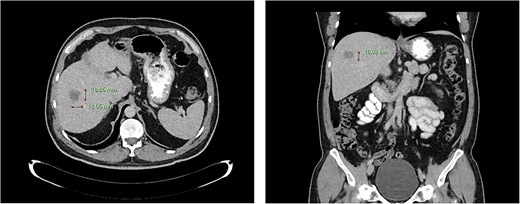

Computed tomography dated 25 September 2012 of the abdomen and pelvis measuring 18.65 mm (anterior–posterior) lesion at liver segment 5/6 in axial (left) and coronal (right) view.